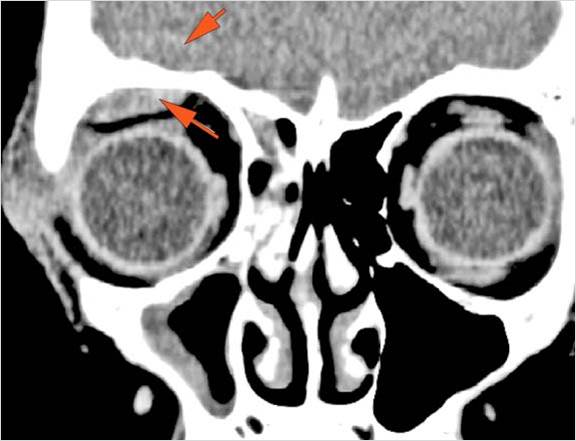

There is evidence of a subperiosteal hematoma along the medial or lateral wall, roof or floor of the orbit.

The circumferential extraconal and the intraconal orbital fat are infiltrated.

Proptosis is present.

The optic nerve has a stretched appearance.

The posterior aspect of the globe is tented.

There is evident general optic sheath swelling or swelling at the junction of the globe and sheath to suggest an optic sheath hematoma.